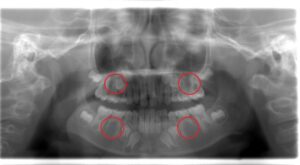

<上下左右5番目の歯(第2小臼歯)が先天性欠如です>

先天性欠如を発見するには、レントゲン撮影が必要です。

レントゲンでこの歯胚が確認できない場合は、先天性欠如の可能性が高くなります。